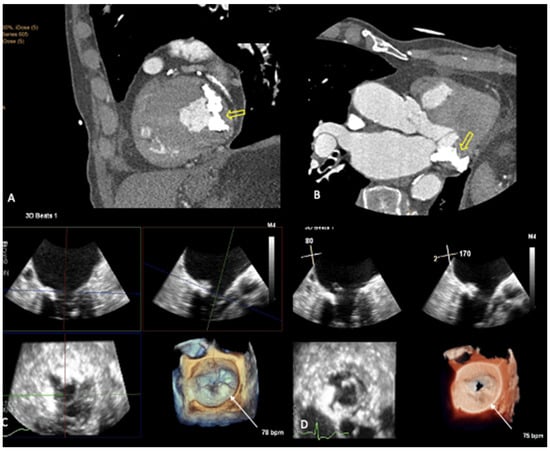

2. Mitral Annular Calcification Imaging

3. Novel 3D Echocardiographic Technique for MAC

4. Maximal Intensity Projection Map Applications

- Prandi, F.R.; Anastasius, M.O.; Zhang, L.; Tang, G.H.; Moreno, P.R.; Romeo, F.; Barillà, F.; Sharma, S.; Kini, A.; Lerakis, S. Novel Three-Dimensional Transesophageal Echocardiographic Method for Mapping Mitral Annular Calcifications. J. Am. Soc. Echocardiogr. 2022, 35, 1004–1005. [Google Scholar] [CrossRef] [PubMed]

- Prandi, F.R.; Dangas, G.D.; Kini, A.; Romeo, F.; Suleman, S.; Khera, S.; Tang, G.H.; Sharma, S.; Lerakis, S. Intraprocedural Mapping of the Mitral Calcium for Positioning and Deployment of Transcatheter Valve-in-Mitral Annular Calcification. JACC Cardiovasc. Interv. 2022, 15, 2341–2343. [Google Scholar] [CrossRef] [PubMed]